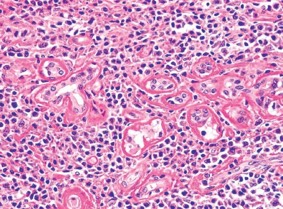

1070. 40-Летний пациент в течение года жаловался на отек в области правой подчелюстной железы, при пальпации область была чувствительна, уплотнена, выполнена резекция правой подчелюстной железы, результаты гистологического исследования образования приведены на микрофотографии

диагноз